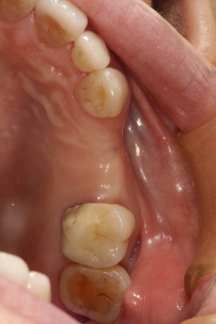

サージカルテンプレートを用いて、すでに決められた位置にインプラントを埋入します。フリーハンドでの埋入に比べ決して埋入位置がずれることはありません。また症例によっては「切らないで」手術を終えることができます。